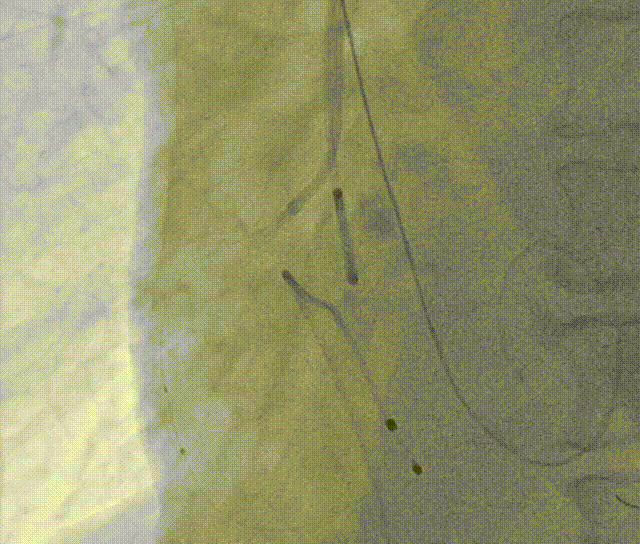

全麻下建立双侧股动脉入路,以右股动脉为主,导丝跨瓣后置换猪尾导管,确定共平面。

图片